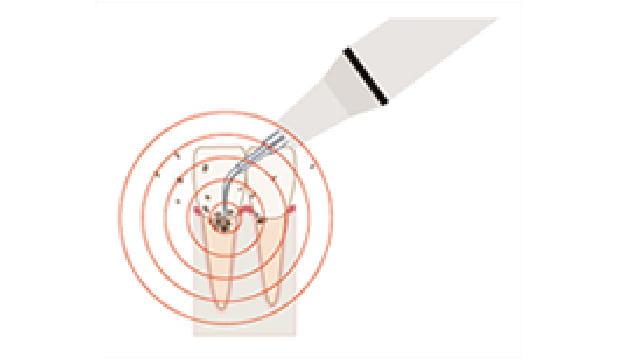

診査(精密検査)

歯周病になってしまった原因と進行状況を調べます。詳しい問診、レントゲン(パノラマX線写真・全顎デンタルX線写真)、歯周ポケットの深さを測定する歯周組織検査、スタディモデル(歯型)、口腔内写真、歯周ポケットから採取したプラークをDNAレベルで検査する歯周病細菌検査、からなります。

※進行状況に応じて必要な検査を行います。

-

パノラマX線写真

-

全顎デンタルX線

写真 -

歯周組織検査